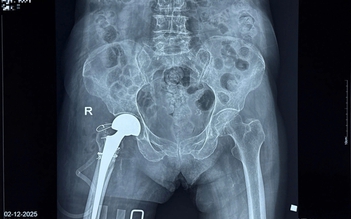

Thay khớp háng thành công cho cụ bà 100 tuổi